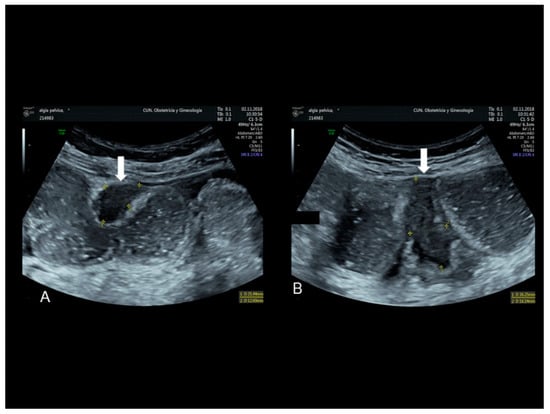

2.2. Scar Endometriosis

This condition includes all cases of endometrial tissue spread within a surgical wound, with reports of ectopic endometrium found within C-section scars, episiotomy scars following spontaneous delivery, and in surgical scars produced by any surgical intervention that may involve manipulation of the endometrial cavity, such as hysterectomy, salpingotomy for ectopic pregnancies and procedures conducted in the first trimester of pregnancy or during the early second trimester [10]. The ectopic tissue can disseminate within the uterine scar or in the thickness of the abdominal muscles or of the subcutaneous tissue. The reported incidence of scar endometriosis is about 3.5% in patients who undergo gynecological surgery and about 0.8% in all women with a previous C-section [10]. Cesarean sections represent the strongest risk factor for scar endometriosis considering the close contact that may commonly occur between endometrial cells and the subcutaneous during this type of surgery [10]. Nonetheless, the incidence of scar endometriosis following a C-section may be underreported since it is not easily diagnosed. Following surgery, the lesion may take from six months to several years to develop and may not present as a palpable and tender mass. Although an abdominal solid mass spotted at ultrasound cannot be immediately considered as endometriosis, if the lesion is located in close proximity to the C-section scar, endometriosis should be included in the differential diagnosis (Figure 1 and Figure 2) [9].

Scar endometriosis may present as a hypoechoic solid nodule with hyperechoic spots or strands which represent fibrosis within the scar tissue, a hyperechoic peripheral ring, spiculated borders and a single vessel entering the nodule from the periphery (Figure 1 and Figure 2) [11,12,13]. In nodules larger than 30 mm, cystic portions and/or fistulous tract, loss of oval or round shape, multiple vascular pedicles, and central vascularization are more frequent [12].

Figure 1. Ultrasonographic images of two nodules (AC) (see white arrows), of scar endometriosis with some color spots (C) due to internal vascularization, infiltrating the external oblique muscle in a woman with a previous cesarean section some years before. Drawing of the location (D).